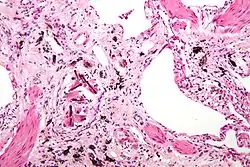

Micrograph of asbestosis (with ferruginous bodies), a type of pneumoconiosis. H&E stain.